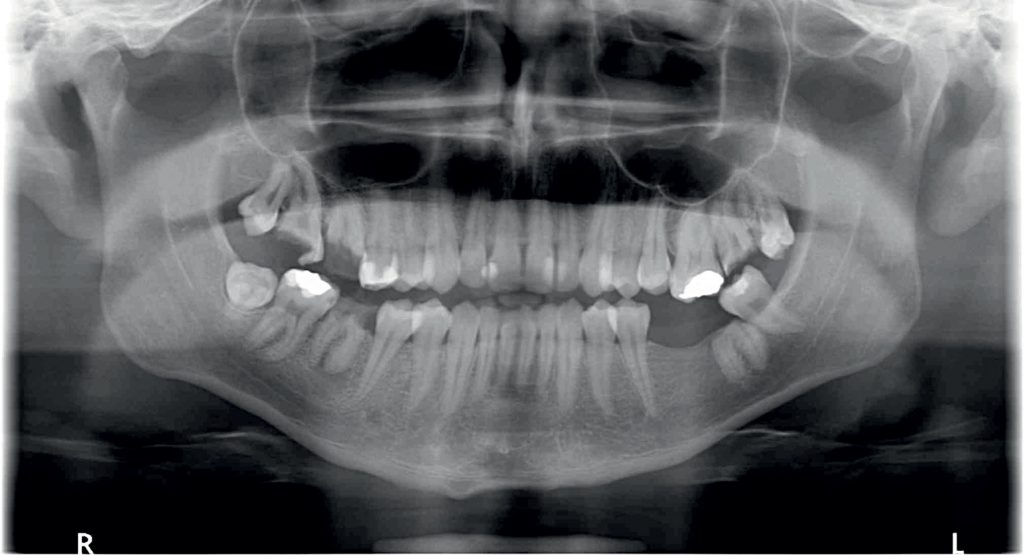

Streszczenie: Materiały uwalniające wapń w ostatnim czasie szturmem podbiły świat stomatologii. Coraz częściej stosuje się materiały z krzemianu wapnia we współczesnej stomatologii dziecięcej, ponieważ oferują znaczącą przewagę nad materiałami historycznie używanymi do wypełnień pulpotomii.

Summary: Calcium-releasing materials have recently taken the world of dentistry by storm. Calcium silicate materials are increasingly being used in modern paediatric dentistry as they offer significant advantages over materials historically used for pulpotomy fillings.

Materiały uwalniające wapń w ostatnim czasie szturmem podbiły świat stomatologii, jednakże ta koncepcja nie jest niczym nowym. Badania związków między strukturą miazgi a wodorotlenkiem wapnia podjęto już w latach 30. XX wieku. Ponieważ wodorotlenek wapnia ma zdolność do zwiększania pH, czyli alkalizacji środowiska, powoduje to uwalnianie czynników wzrostu, które pomagają w naprawie zębiny, dlatego podkłady z wodorotlenku wapnia od dawna stosowano do przykrycia miazgi. Działanie wodorotlenku wapnia opiera się na uwalnianiu jonów hydroksylowych, które alkalizują środowisko, działając jednocześnie bakteriobójczo. Początkowym skutkiem jego [...]